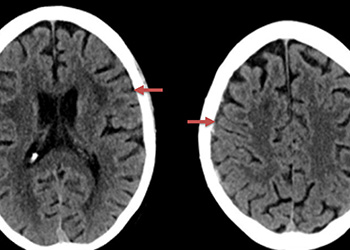

Figure 1. A) 6 weeks post mild trauma B) 4 weeks post mild trauma demonstrate stable subacute subdural collections with mild growth and sulcal effacement.

A man in his 80s developed mild dizziness and headache following incidental trauma working in his garage one day. He presented several weeks later to the ER and was diagnosed with bilateral subdural hematomas, which were initially managed with observation, low dose Decadron, considering the mildness of symptoms, advanced age, and history of CLL with thrombocyptopenia (<100k). Over the next 4 weeks, the collections remained relatively stable with evidence of slight growth (10 to 12 mm thickness, and 2 mm right to left shift) on NCT (Figure 1. A and B).